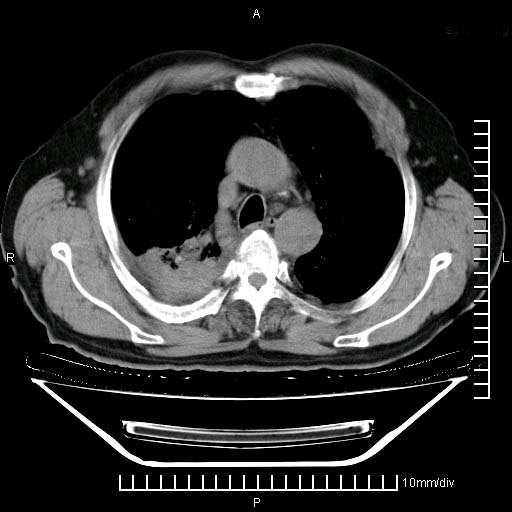

标题: CT24043:胸部增强:男性,60岁

既往肺结核,近10几天,咳嗽,咳痰,右侧胸痛,疼痛较明显,右上肺斑块考虑结核灶胸膜粘连,增强,可惜动脉期没有定好,未见强化,可延迟4分后又见较明显强化,中心见低密度影,如果说结核是边缘强化,可这个灶强化的面积挺大的,让人很挠头。

1)两肺继发性肺结核。2)右侧胸膜增厚+少量胸腔积液。